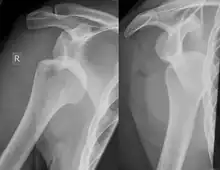

Lesão de Hill-Sachs, ou Fratura Hill-Sachs, é uma depressão cortical na cabeça do úmero posterolateral. É o resultado de impactação forte da cabeça umeral luxada contra a glenóide anterior quando o úmero é luxado anteriormente.

A lesão está associada exclusivamente com a luxação glenoumeral anterior.[2] Quando o úmero é impulsionado à partir da cavidade glenoumeral, este impacta a cabeça, relativamente macia contra a borda anterior da glenóide. O resultado é um torrão, sulco ou achatamento no aspecto posterolateral da cabeça do úmero, geralmente oposto ao processo coracóide. O mecanismo que leva à luxação do ombro é geralmente traumático, mas pode variar, especialmente se houver história de deslocamentos anteriores. Esportes, quedas, convulsões, brigas ou virar na cama podem ser causas de deslocamento anterior.